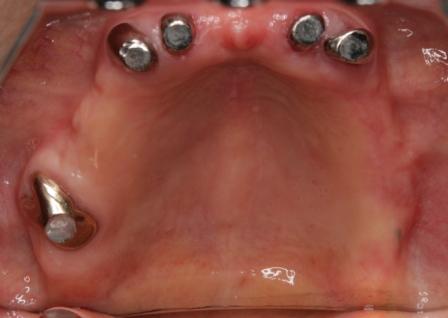

インプラント 世界的にトップシェアであり臨床研究が最も行われている(エビデンスのある)

ストローマン社インプラントを使用しています

インプラントオペ料金 253,000円(税込) 診査・診断・埋入手術含む

インプラント上部構造 132,000円(税込)

サイナスリフト 220,000円(税込)

オステオトームテクニック 88,000円(税込)

骨造成術(GBR) 33,000円~

88,000円(税込)